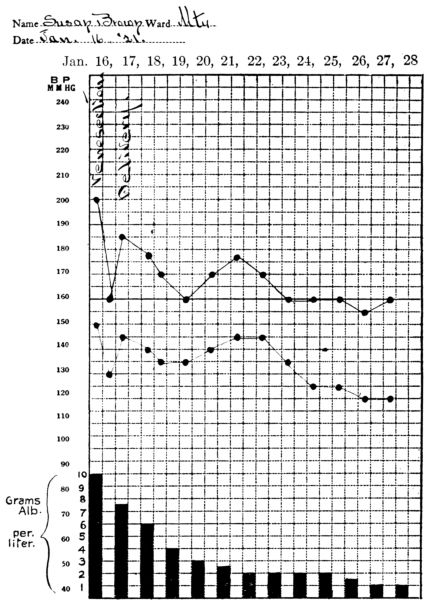

| 2. | Showing persistence of high blood pressure and albumen in the urine, after delivery, in nephritic toxæmia with convulsions | 206 |